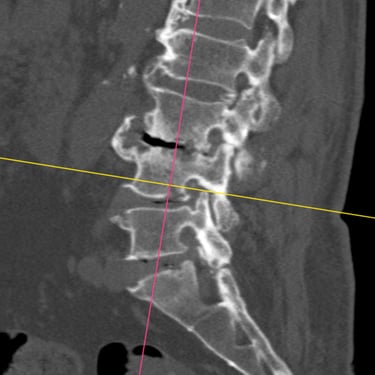

🧠 Listesis L4–L5 con Estenosis Severa: Estabilización con Fijación Transpedicular (FTP) y Fusión Intersomática Transforaminal (TLIF)

La listesis L4–L5 con estenosis severa provoca dolor lumbar e inestabilidad con compresión nerviosa. La fijación transpedicular (FTP) y la fusión intersomática transforaminal (TLIF) permiten descomprimir el canal espinal, estabilizar la columna y mejorar la función de forma segura y progresiva.